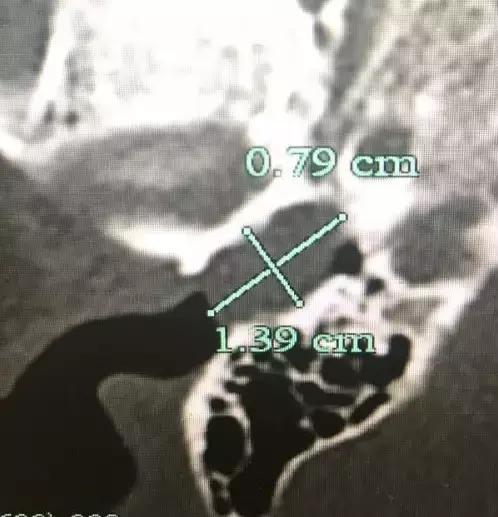

孩子耳朵的CT照